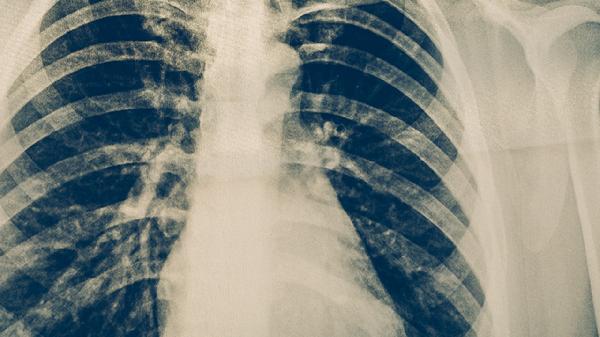

结核病是由结核分枝杆菌感染引起的慢性传染病,不同部位的结核病治疗原则相似,均需遵循早期、联合、适量、规律、全程的用药原则。肺结核作为最常见类型,标准治疗方案通常采用异烟肼片、利福平胶囊、吡嗪酰胺片、乙胺丁醇片四联药物,强化期治疗2个月后转为巩固期治疗4个月。骨结核因病灶血供较差,药物渗透困难,疗程需延长至9-12个月,严重骨质破坏者可能需联合手术清创。肾结核治疗周期约6-9个月,若出现肾盂积水或肾功能严重受损,可能需介入引流或肾部分切除术辅助治疗。治疗期间需定期监测肝功能、尿酸等指标,骨结核患者还需通过影像学评估骨质修复情况。